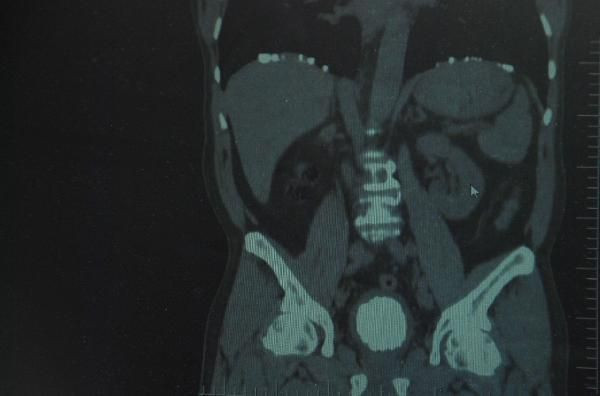

ELAZIĞ'da, idrar yollarında yaşadığı rahatsızlık nedeniyle hastaneye başvuran Haydar Şimşek'in (67), mesanesinde 10 santimetre çapında 220 gram ağırlığında taş olduğu ortaya çıktı. Taş yapılan ameliyatla Şimşek'ten alındı.

Diyarbakır'ın Çüngüş ilçesinde oturan Haydar Şimşek, 10 yıldır idrar yollarında yaşadığı rahatsızlık nedeniyle Elazığ'da özel hastaneye başvurdu. Hastanede görevli Prof. Dr. Mustafa Kemal Atikeler, tarafından yapılan tahlil ve tetkiklerin ardından çekilen tomografi sonucunda Şimşek'in mesanesinde 10 santimetre boyutunda taş tespit edildi. Yapılan ameliyatla Şimşek'in mesanesindeki taş tek parça halinde çıkarıldı.

Ameliyatı gerçekleştiren Prof. Dr. Mustafa Kemal Atikeler, taşın 10 santimetre çapında 220 gram ağırlığında olduğunu ifade ederek, "30 yıllık meslek hayatımda gördüğüm en büyük mesane taşı diyebilirim. Yaklaşık 10 santimetre çapında. Bayağı büyük ve sert bir taş. Hastamızı ameliyat ettik ve mesanesindeki taşı çıkarttık. Hastamız şu an çok rahat ve yarın akşam taburcu edeceğiz" dedi.